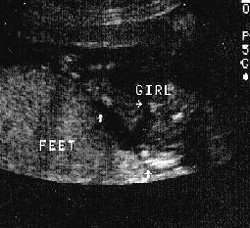

ثانيا : البنت

الاسبوع ال16